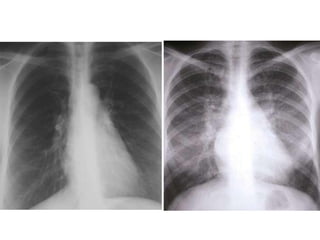

XQ TIM PHỔI

 Hình bóng tim to, huyết quản phổi tăng đậm,

 Hình cánh bƣớm hai rốn phổi, đƣờng Kerley B

ở hai phế trƣờng...

XQUANG TIM PHỔI THẮNG

Cung dƣới trái phồng và kéo dài ra

Phổi mờ hai phổi nhất là vùng rốn phổi

Đƣờng Kerley B

Hình “cánh bƣớm” kinh điển ở hai rốn phổi khi phù phổi